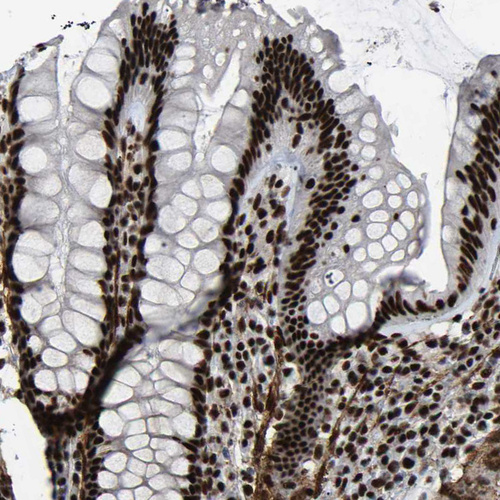

Immunohistochemical staining of human endometrium shows strong nuclear positivity in glandular cells.